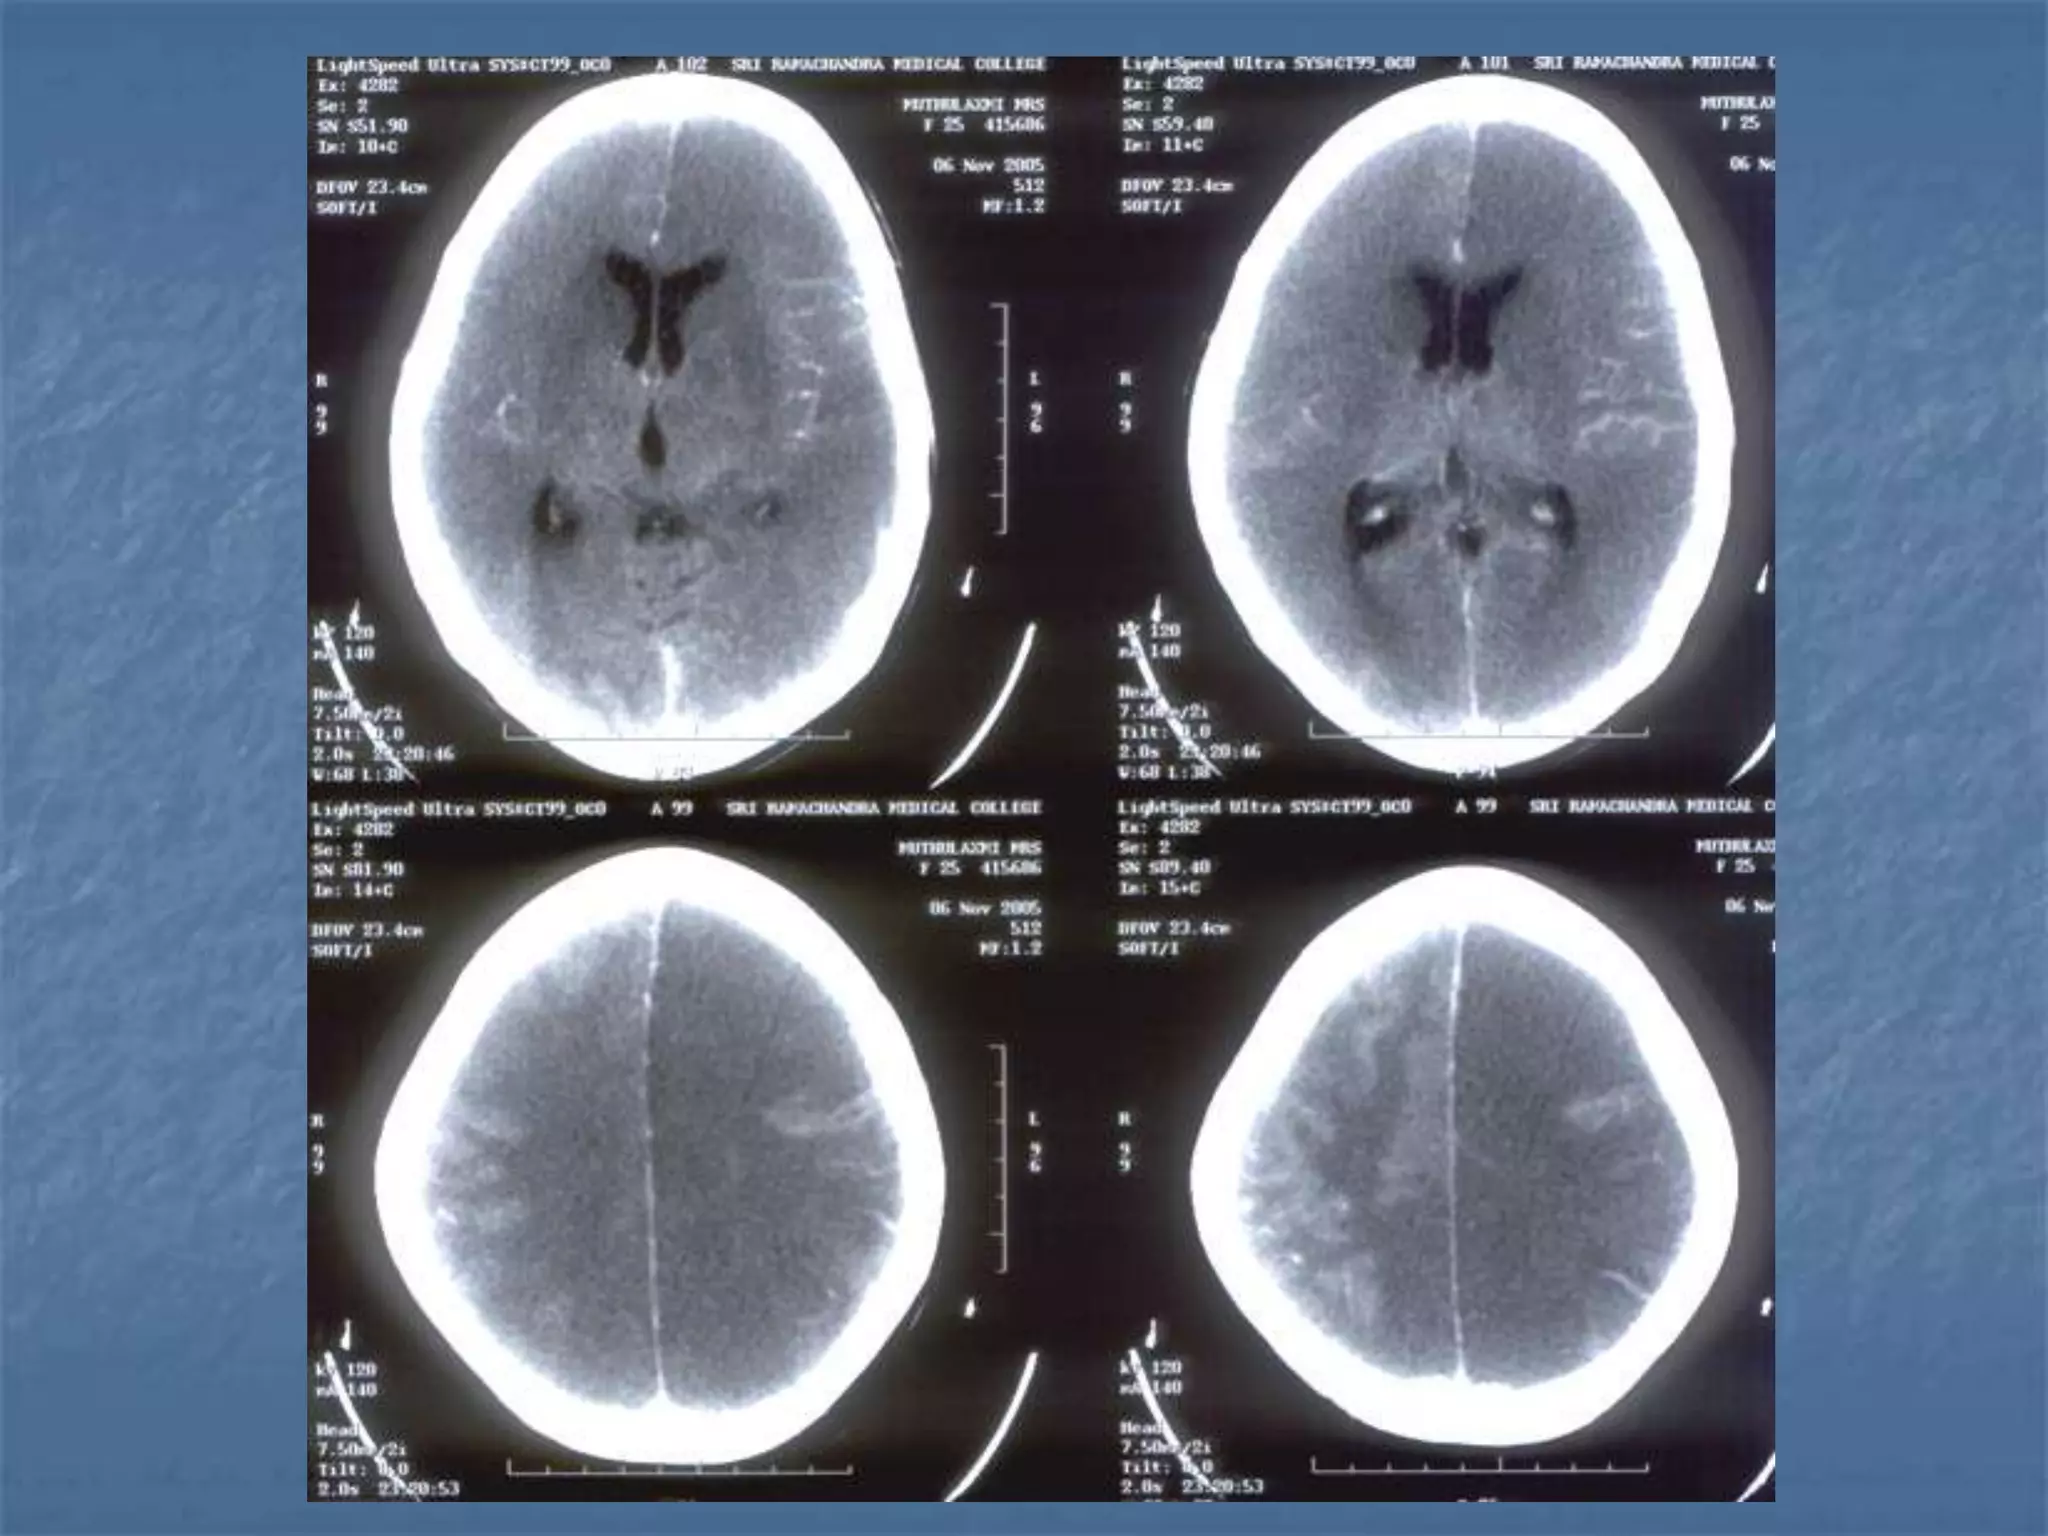

25 yr old lady c/o fever and altered sensorium x 1

wk. Had 1 episode of GTC seizures. Admitted

elsewhere , LP done showed proteins-55 mg % and

sugar –105 mg % ..

ABG- pH – 7.55

HCO3 – 28.3 , PCO2-32.9, PO2 –322.9,SPO2-99.8

CT – Normal

Discharged at request.

H/o fever,headache and vomitting on and off x 5

mths -

 O/E – GCS – E1V1M5

BP – 140/100 , PR – 116

Pupils – 4mm dilated , sluggish light reaction

Neck Rigidity +

Kernig’s & Brudeski’s - ve

 Hb-13.5

 TC- 12,200

 Platelets-4.2

 MP/MF – negative

 BUN, creatinine – normal

 Urine R/E – proteins +++, pus cells 5-8

 Coagulation Profile - WNL

 134/3.4/26/102